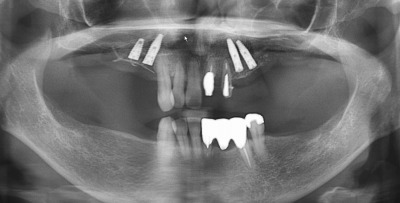

先月左の上はすでにインプラントを2本入れまして、今日は右上に2本のインプラントを入れました。

鼻腔が近くて当初1本の予定でしたが、歯肉側に少し骨を造って (GBR) 2本にしました。ギリギリでした。

多少でも骨が残ってまいすからよかったです。下の奥歯は5月と6月にインプラントを入れる予定です。